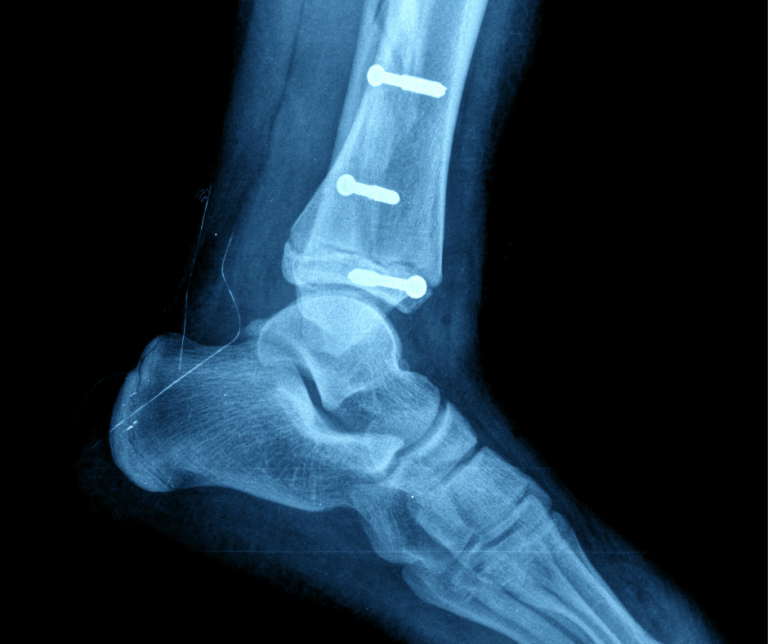

Surgical Screws: Supporting Healing and Ensuring Stability

When people hear about the use of surgical screws, their first reactions tend to stem from what they’ve seen in horror movies, not what they’ve read in medical journals. Yet despite some unfortunate negativity centered on their use in surgical procedures, screws have a very important and therapeutic role in foot and ankle surgery, helping…